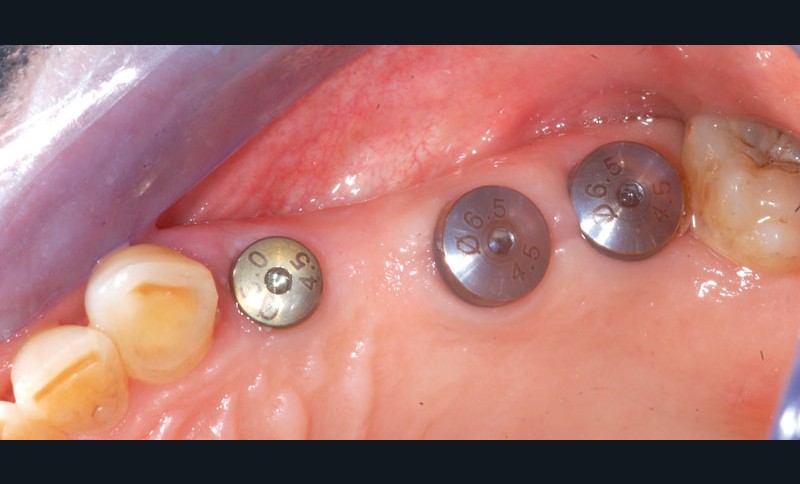

Au maxillaire, 3 implants Astra Tech Implant EV (Dentsply) sont posés en un temps chirurgical. Une empreinte pick-up sera réalisée après 4 mois de cicatrisation.